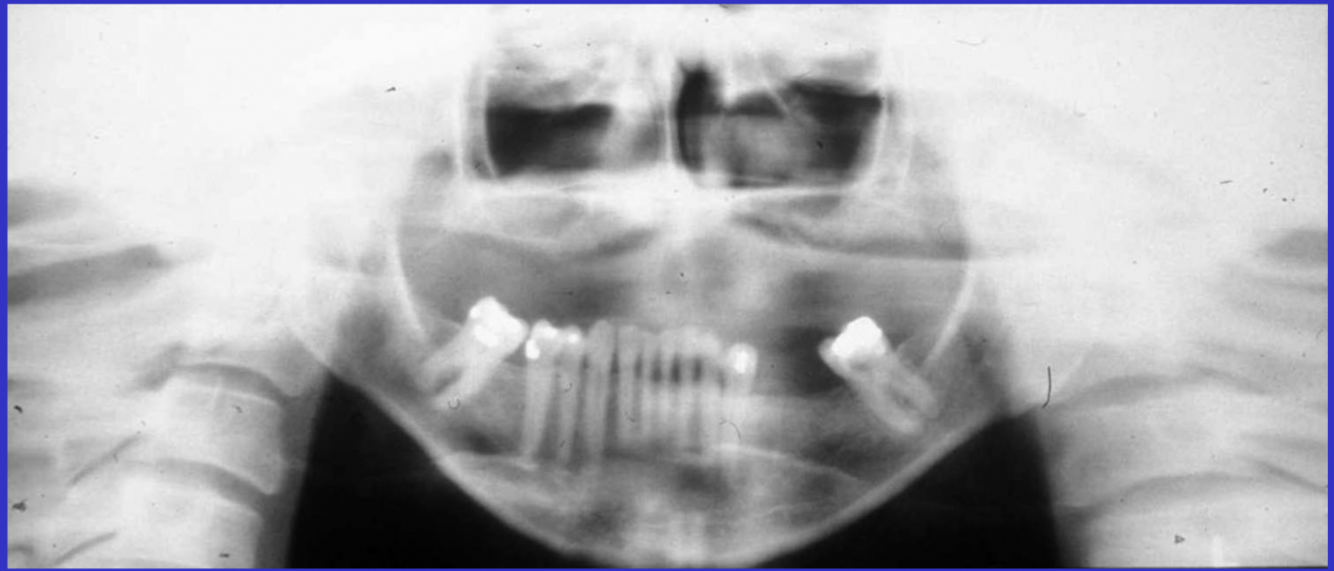

24

What are the errors in this radiograph? What is the cause of these errors?

A

1. anterior teeth widened and blurred

2. inferior tubercles and meati spread across maxillary sinuses

3. condyles close to or cut off side of image

cause: patient too far back